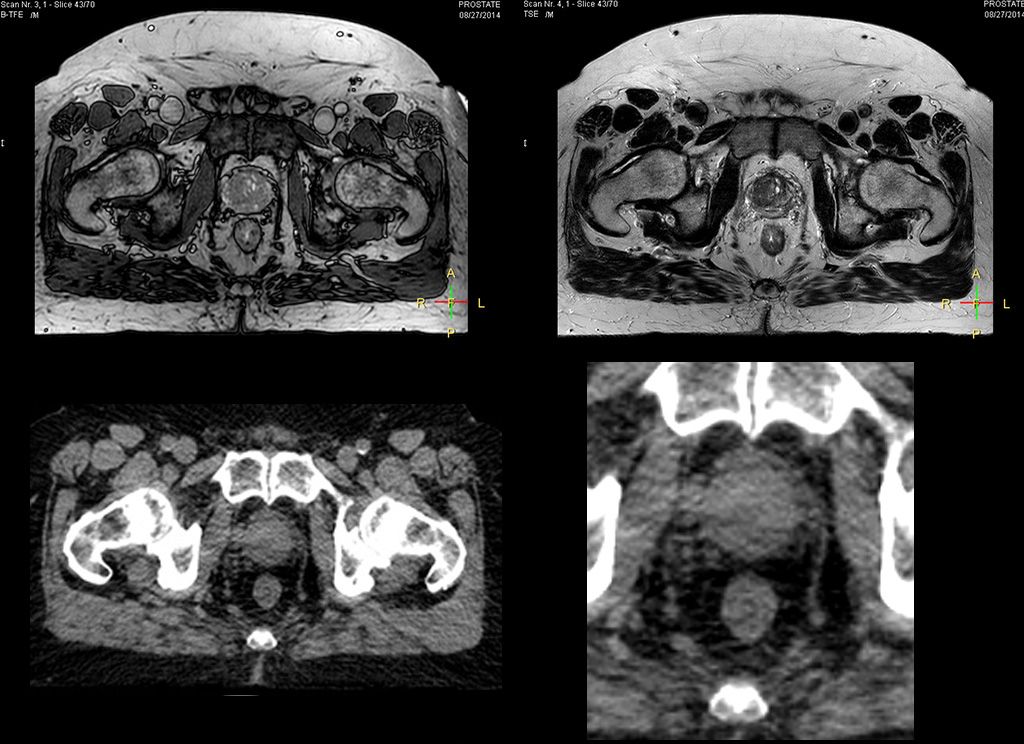

“We currently use MR-RT mainly in the abdomen and pelvis region: prostate, colorectal, pancreatic, cervical, and liver. Also in the brain, we are starting to use it,” says Dr. Yan.

Impressive clinical benefits for prostate

“The biggest problem for CT-based planning, especially in prostate, is you can’t see the cancer very well,” says Dr. Stevens. “On CT it can be quite challenging to see the edge of the prostate especially at the apex. When the edge of the prostate can’t be delineated well on CT, radiation oncologists will increase their margins a little bit so they don’t miss it, but that can also increase toxicity.”

“Using MR, the prostate is well delineated. We quickly see the edges of cancerous tumors like in prostate cancer, and as normal structures can be defined, we can optimize the treatment plan to protect these organs and their normal function. This can potentially improve the outcome. And it improves workflow as well. We can contour more quickly, confident that the tumor is going to be in the field.”

“The Ingenia 3.0T MR scanner provides high resolution allowing us to make scans fast for the patients. It also gives the potential to include methods like MR spectroscopy and diffusion weighted Imaging, which we’re in the process of doing right now,” Dr. Stevens adds.

“When a patient registers, first CT simulation and MR simulation are done, followed by CT-MR registration on Pinnacle3. Then the target and normal organ delineation is performed on MR images. Meanwhile we create a reference CT image for online treatment and localization correction. During the treatment phase we can perform additional MRI scans to visualize the anatomy changes and create an adaptive plan. This plan basically adapts the treatment plan to the changes.”